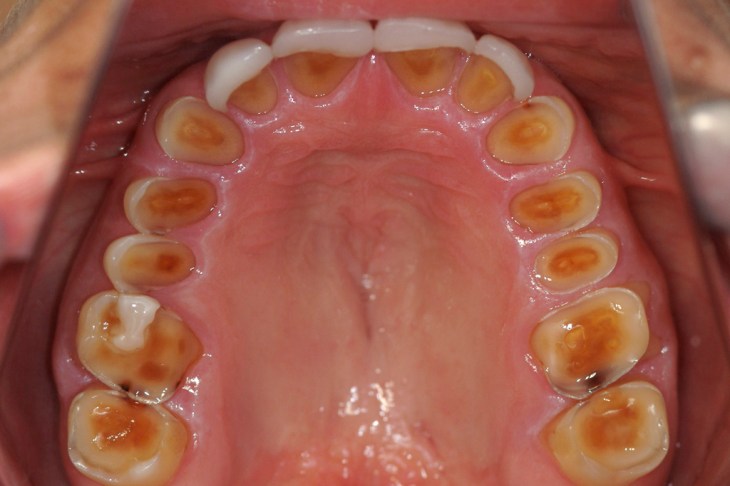

- Aparência. O efeito depende do tipo de desgaste do dente , mas podem incluir a desgaste das extremidades e uma maior transparência das pontas dos dentes da frente. As superfícies podem aparecer suaves, arredondadas e ” polidas “;

- Sensibilidade ao calor e ao frio. Isto pode ocorrer quando o esmalte protector exterior se desgasta expondo a dentina mais sensível . Nem sempre ocorre, especialmente se o desgaste está a progredir lentamente .